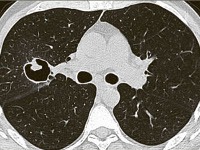

Одиночные или множественные сферические тени обнаруживаются на рентгенограммах и КТ легких, чаще всего располагаются в верхних долях с одной или обеих сторон. Патогномоничным признаком мицетомы является симптом полумесяца - наличие воздушной полосы, которая отделяет большую часть массы гриба от стенки полости. Когда положение тела пациента изменяется, наблюдается внутриполостное движение шарика, образованного аспергиллусом - симптом погремушки.